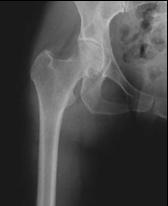

Joint cartilage is a tough, smooth tissue that covers the ends of bones where joints are located. It helps cushion the bones during movement, and because it is smooth and slippery, it allows for motion with minimal friction. Osteoarthritis, the most common form of arthritis, is a wear-and-tear condition that destroys joint cartilage. Sometimes as the result of trauma, repetitive movement, or for no apparent reason, the cartilage wears down, exposing the bone ends. This can occur quickly over months or may take years to occur. Cartilage destruction can result in painful bone-on-bone contact, along with swelling and loss of motion. Osteoarthritis usually occurs later in life and may affect only one joint or many joints.

A hip replacement is an operation that removes the arthritic ball of the upper femur (thighbone) as well as damaged bone and cartilage from the hip socket. The ball is replaced with a metal ball that is fixed solidly inside the femur. The socket is replaced with a plastic or metal liner that is usually fixed inside a metal shell to create a smoothly functioning joint.